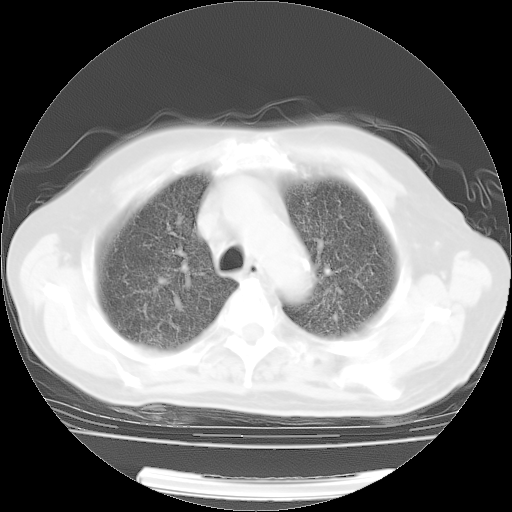

4月14日肺部CT

23.JPG

24.JPG

25.JPG

26.JPG

肺部CT平扫未见异常。